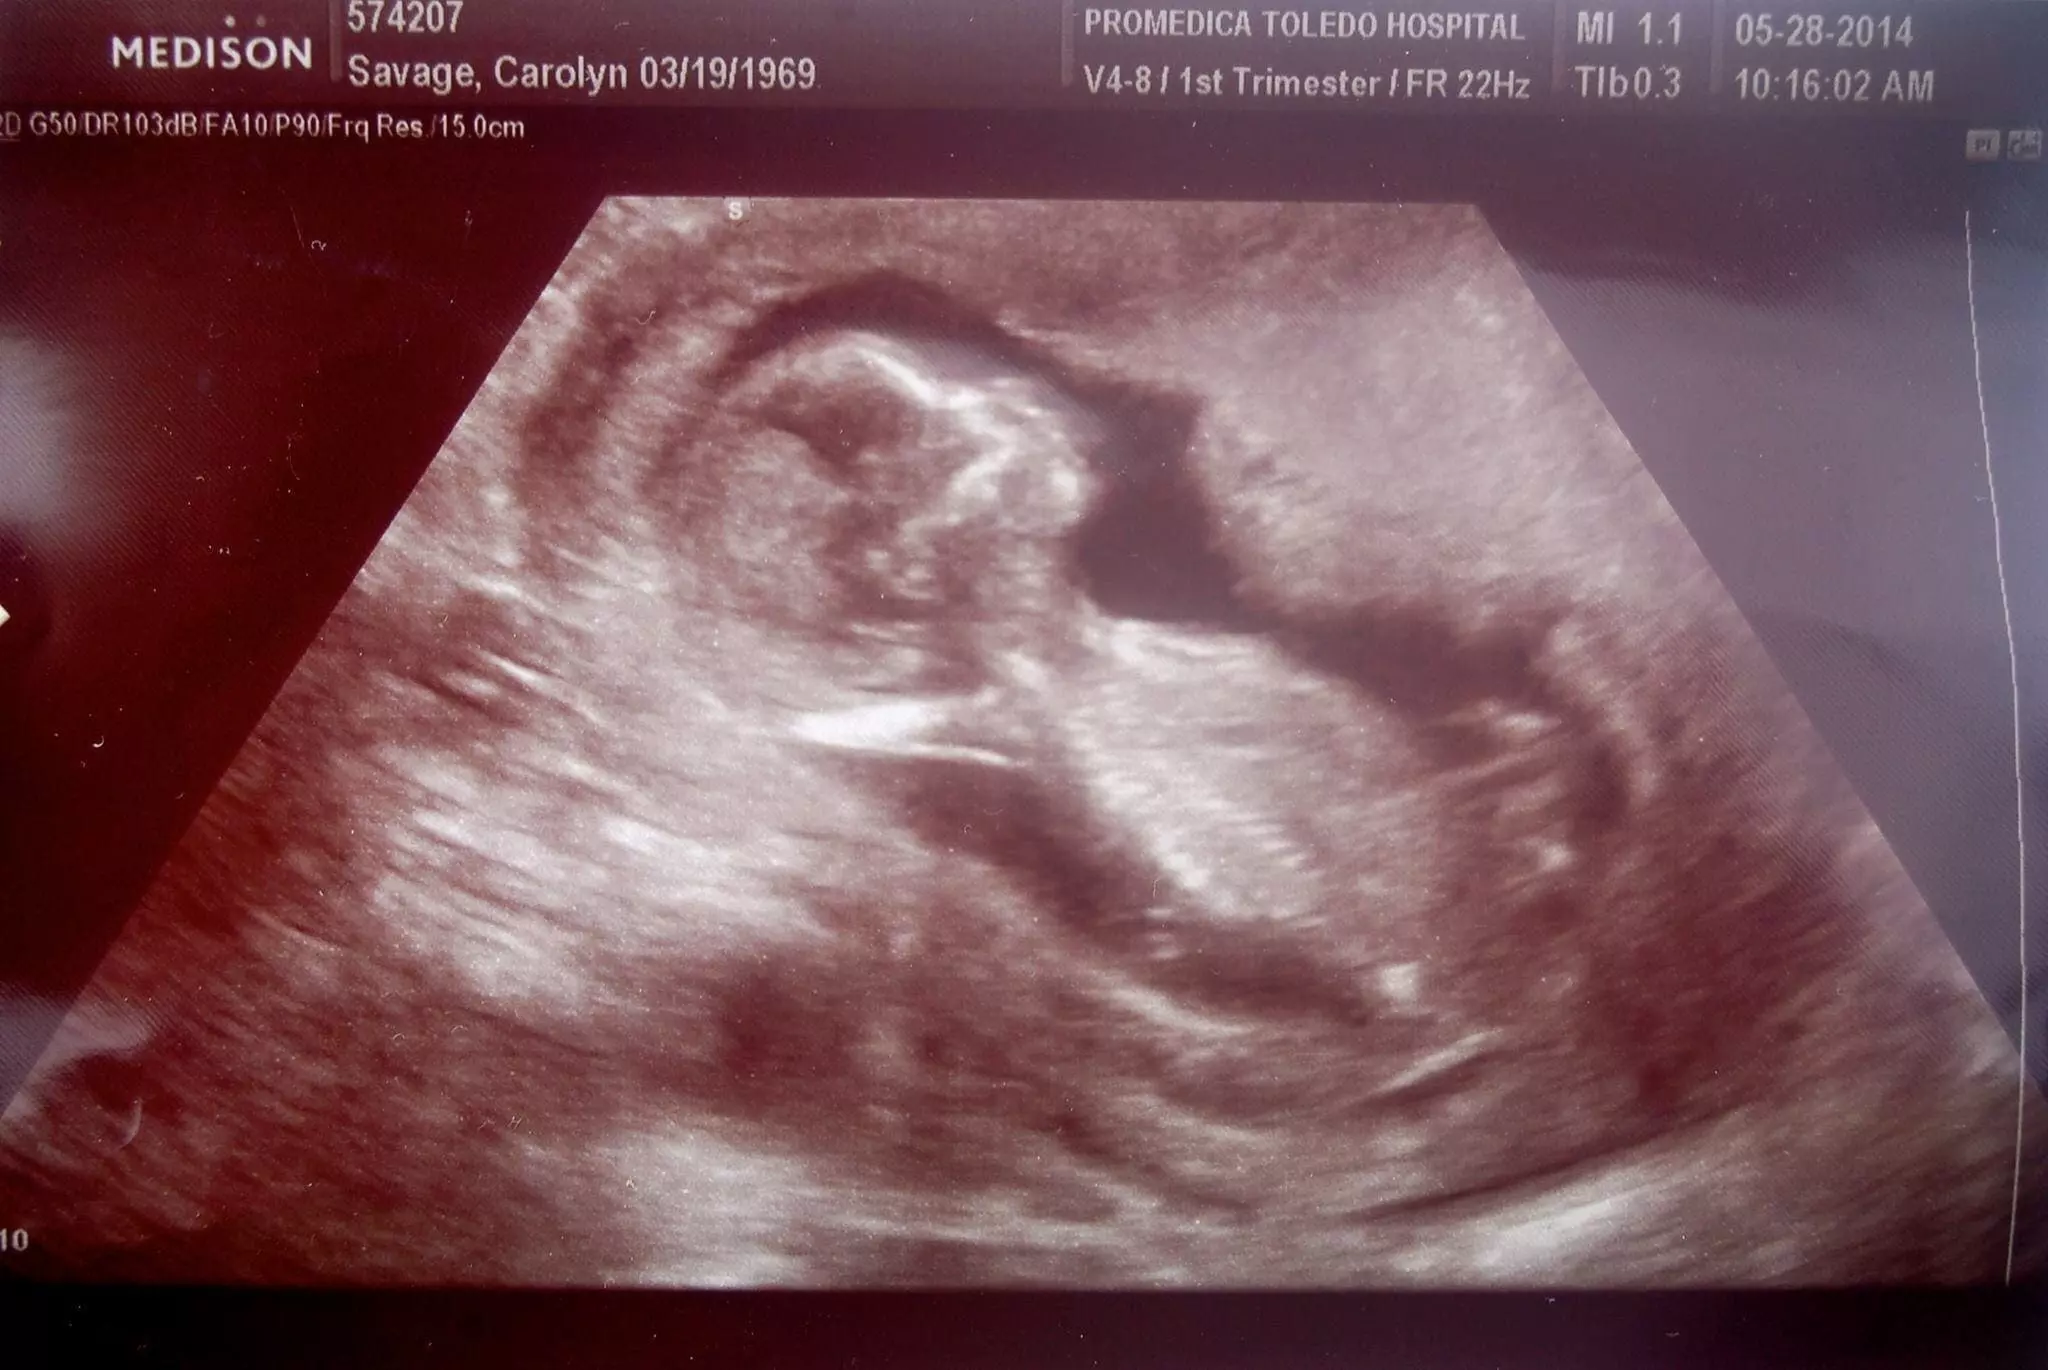

Alors que Carolyn et son mari croyaient ne plus pouvoir enfanter par voie naturelle, voici qu’en 2014, un autre miracle se produit. Carolyn effectue un test de grossesse et n’en croit pas ses yeux. Elle est enceinte d’un huitième enfant ! À 45 ans, Carolyn a mis au monde le petit Nicholas, par voie naturelle.